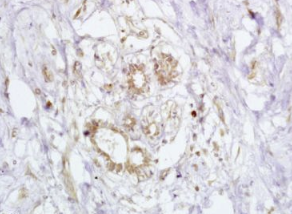

组织/细胞:人乳腺癌;4%多聚甲醛固定石蜡包埋;

抗原提取:柠檬酸缓冲液(0.01M,pH 6),15min煮沸,用3%过氧化氢阻断内源性过氧化物酶30min;37℃下阻断缓冲液(正常山羊血清)20 min;

孵育:抗-BRCA2/FANCB多克隆抗体,未结合1:200,在4°C下过夜,然后与二级抗体结合,DAB染色。